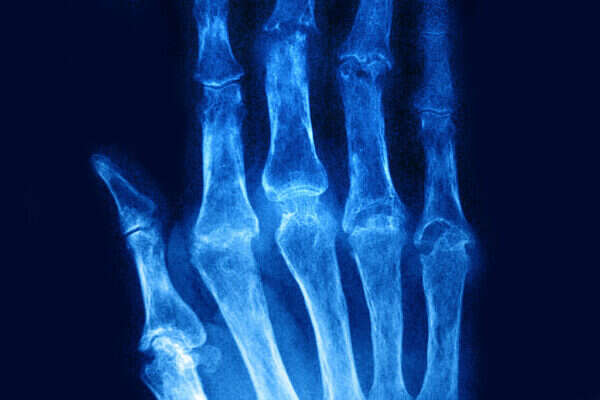

ביהדות אומרים שהגוף מורכב מ-248 (רמ"ח) איברים ו-365 (שס"ה) גידים – ושוכחים מספר דומה (בין 250 ל-350) מפרקים, שהם חלק קריטי ממערכת התנועה שלנו, אך לרוב איננו מקדישים להם מחשבה עד שמופיעים כאבים או בעיות.